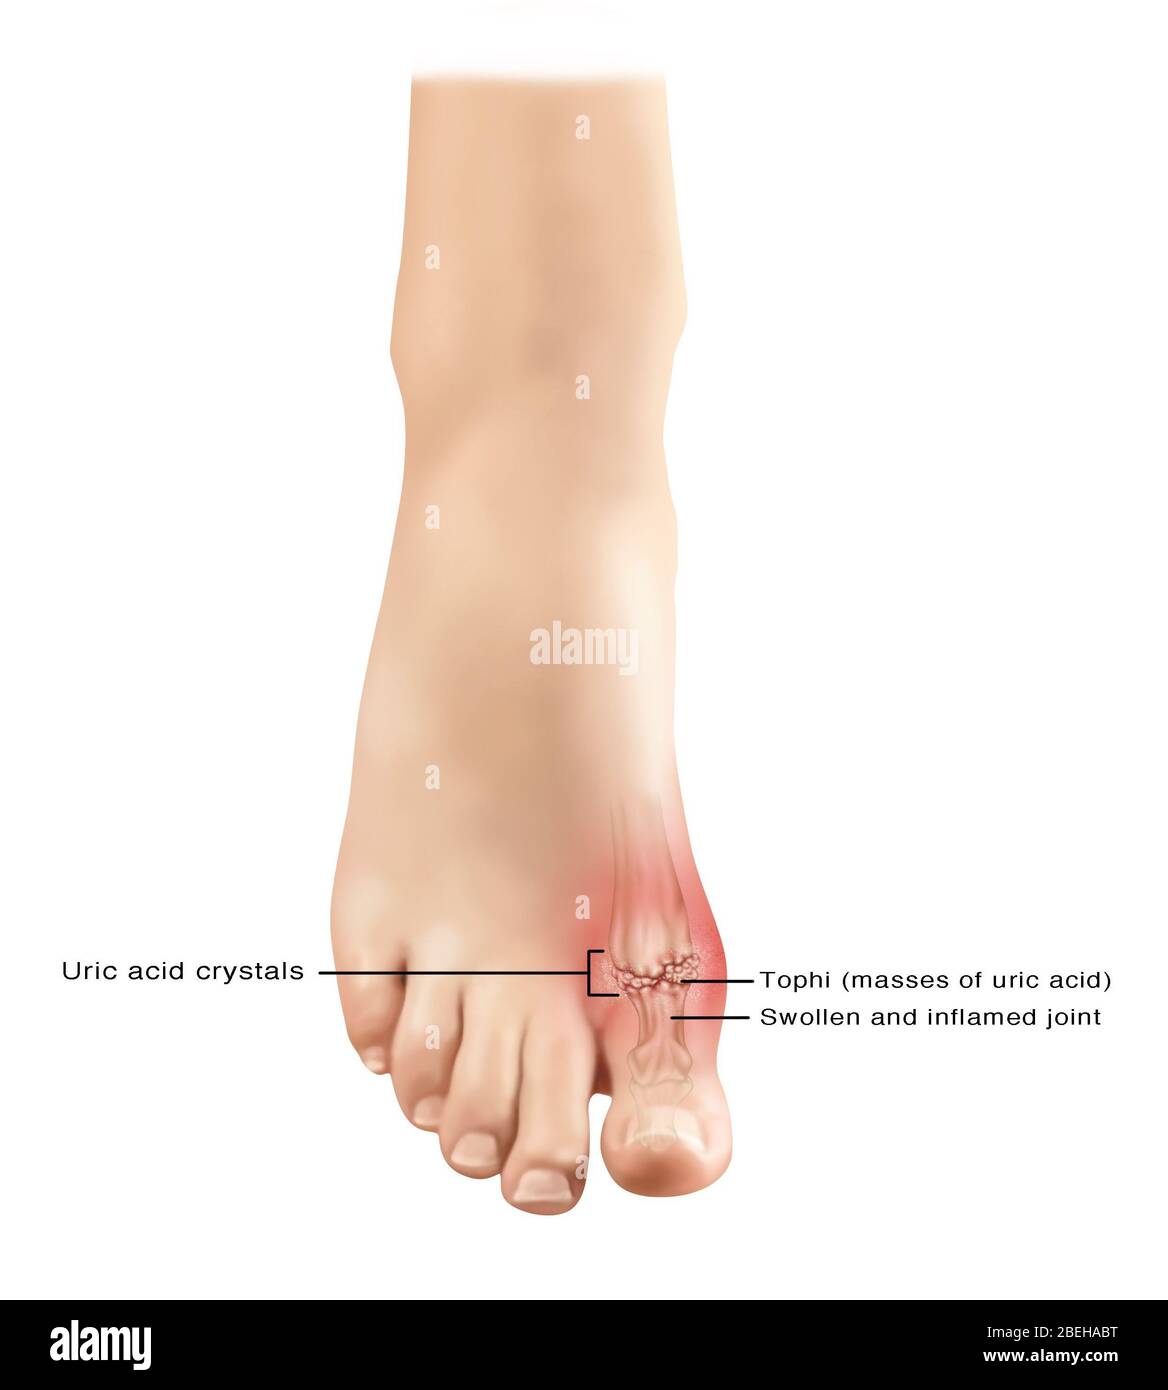

Gout in Foot, Illustration Stock Photohttps://www.alamy.com/image-license-details/?v=1https://www.alamy.com/gout-in-foot-illustration-image353193896.html

Gout in Foot, Illustration Stock Photohttps://www.alamy.com/image-license-details/?v=1https://www.alamy.com/gout-in-foot-illustration-image353193896.htmlRF2BEHABM–Gout in Foot, Illustration

Gout in Foot, Illustration Stock Photohttps://www.alamy.com/image-license-details/?v=1https://www.alamy.com/gout-in-foot-illustration-image353193985.html

Gout in Foot, Illustration Stock Photohttps://www.alamy.com/image-license-details/?v=1https://www.alamy.com/gout-in-foot-illustration-image353193985.htmlRF2BEHAEW–Gout in Foot, Illustration

Gout in Foot, Illustration Stock Photohttps://www.alamy.com/image-license-details/?v=1https://www.alamy.com/gout-in-foot-illustration-image353193900.html

Gout in Foot, Illustration Stock Photohttps://www.alamy.com/image-license-details/?v=1https://www.alamy.com/gout-in-foot-illustration-image353193900.htmlRF2BEHABT–Gout in Foot, Illustration